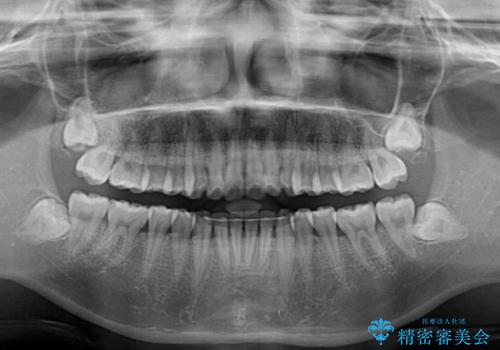

- 全体的な歯列の叢生を気にして来院された患者様です。

奥歯の咬み合わせを見ると、片方は上顎が下顎に対して相対的に前方にある状態でした。

咬み合わせを改善するためには、上顎臼歯を後方に移動させた咬み合わせにする必要があります。

インビザライン単体で改善することも可能ですが、ディープバイトのためインビザライン単体で達成する可能性が低いと考えられたため、カリエール・ディスタライザーという補助装置を併用して、より確実性を上げることとしました。

奥歯の咬み合わせ改善後に、インビザラインにて歯列を整えることとしました。

カリエールディスタライザーを併用したことで、確実かつ短期間で治療を終えることができました。